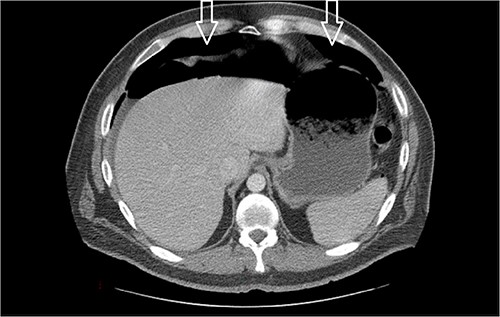

Eleven days post-discharge, he presented to the ER with the same symptoms. CT once again demonstrated pneumoperitoneum (see Fig. 3). Perforated hollow viscus structure is suspected; however, no rim-enhancing abscess is evident. Given his previous two negative ex-laps, a repeat EL was deferred. A conservative treatment plan of pneumoperitoneum was implemented for IP.

Amount of pneumoperitoneum increased compared with previous CTs.